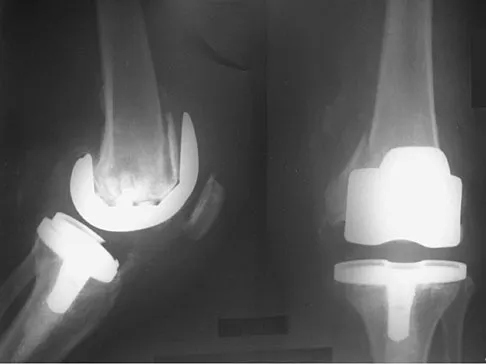

A 75-year-old woman who fell on her right knee now reports pain and is unable to bear weight. History reveals that she underwent total knee arthroplasty on the right knee 6 years ago. Radiographs are shown in Figure 5. Management should now consist of

Explanation

The radiographs show a loose femoral component with an associated medial condyle distal femoral fracture. The treatment of choice is open reduction and internal fixation with revision of the femoral component because of the femoral component loosening. Moran MC, Brick GW, Sledge CB, et al: Supracondylar femoral fracture following total knee arthroplasty. Clin Orthop 1996;324:196-209. McLaren AC, DuPont JA, Schroeber DC: Open reduction internal fixation of supracondylar fractures above total knee arthroplasties using the intramedullary supracondylar rod. Clin Orthop 1994;302:194-198.